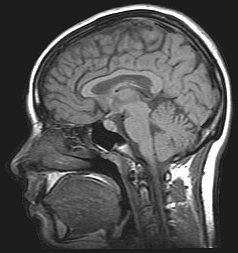

核磁気共鳴画像法 Wikipedia